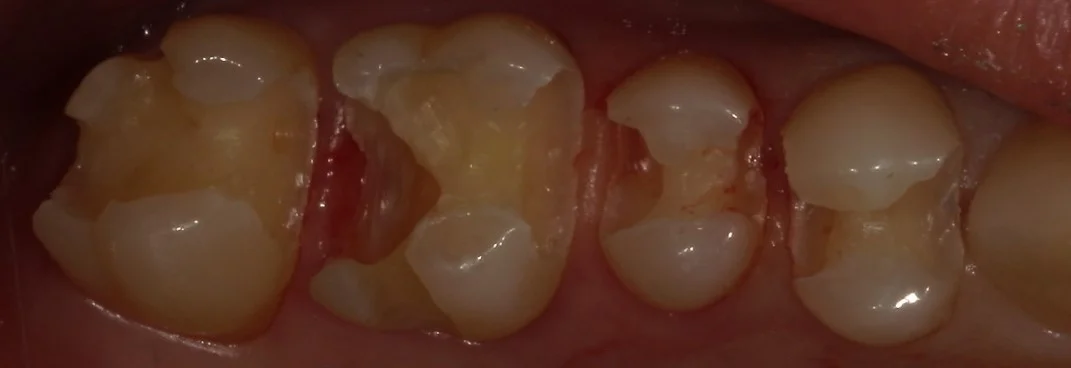

すこし暗いので分かりづらいですが・・・

今回処置を行ったのはこの金属の部分です。

さて、金属を外したのがこちらです。

全体的に金属を白い詰め物に。|坂寄歯科医院(取手市藤代) - 画像2

歯の周りで黒くなっている部分のほとんどは虫歯ではなくセメントが黒く着色しているだけの状態ですが・・・

これは要はセメント部分が劣化しているから起こっているのです。

その為、その劣化した部分から内面に向かって虫歯が入り込んでいる場合が多々あります。

今回のこのお写真でも、非常に大きく虫歯が入り込んでいました。